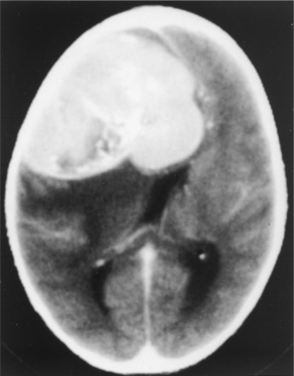

Figure 30-9 Computed tomographic scan with contrast of a meningioma in a patient who presented with mild cognitive deficits, illustrative of the size a slow-growing tumor can attain in the brain. The tumor was completely resected. (From Goldman LM, Ausiello D, eds: Cecil textbook of medicine, ed 22, Philadelphia, 2004, Saunders.

Meningiomas, because of their proximity to or invasion of the bone, are known to provoke a local osteoblastic response termed hyperostosis. This may cause a profuse local thickening of the skull. Fig. 30-10 shows diffuse reactive hyperostosis as well as facial distortion from the growing meningioma.

Figure 30-10 A, Upper eyelid edema, mild proptosis, and downward displacement of the eye due to en plaque sphenoid wing meningioma. B, Computed tomographic scan of the same patient demonstrating lytic bone lesions and diffuse reactive hyperostosis due to bone infiltration by meningioma. (From Abeloff MD, Armitage JO, Niederhuber JE, et al: Clinical oncology, ed 3, Philadelphia, 2004, Churchill Livingstone.)